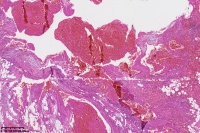

海绵状血管瘤?

楼主 发表于 2023-02-19 09:49

性别

男

年龄

31岁

临床诊断

一般病史

颈部包块

标本名称

大体所见

图2

同意楼主意见,海绵状血管瘤。